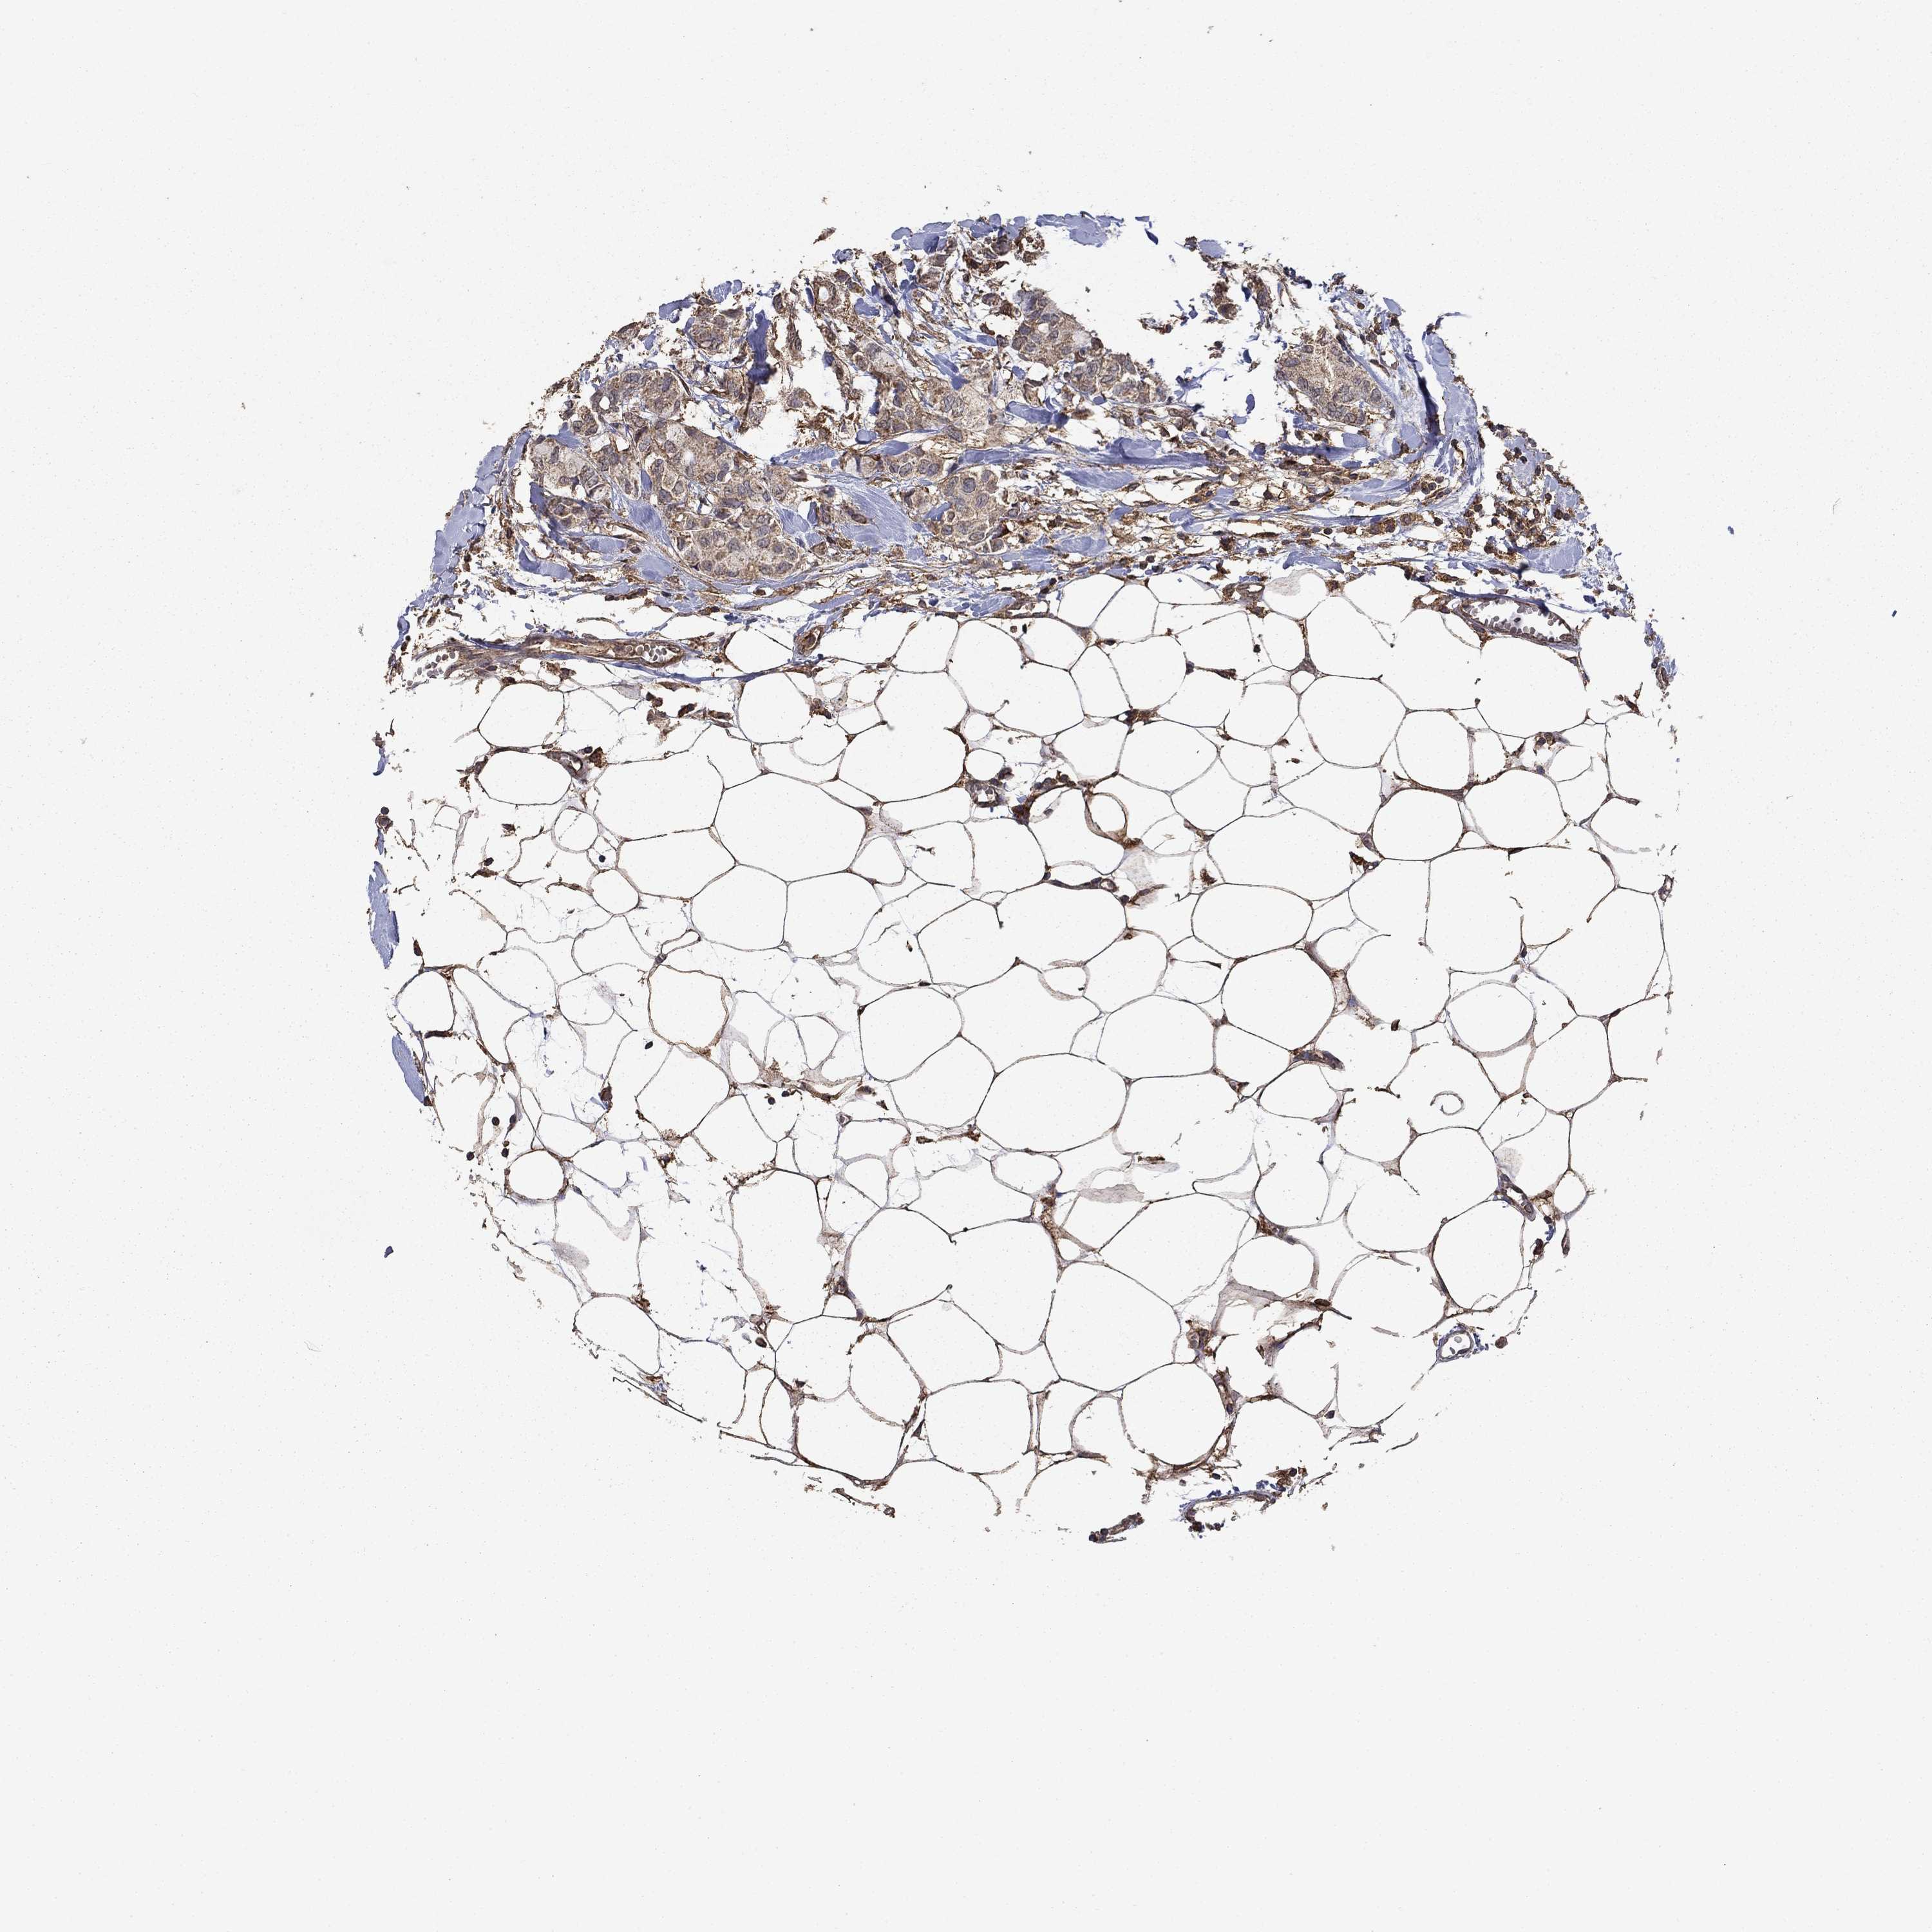

CANCER BREAST CANCER Show tissue menu

BRCA TCGA BRCA VALIDATION PROTEIN EXPRESSION